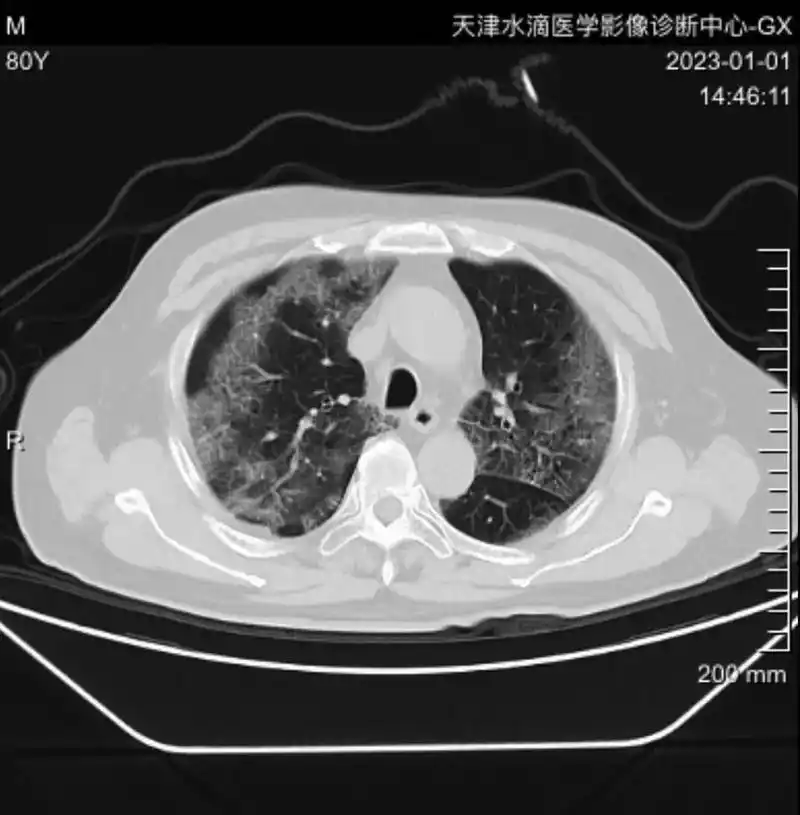

阳康后到我们单位检查胸部ct的患者.有很大一部分得了新冠肺炎 - 抖音